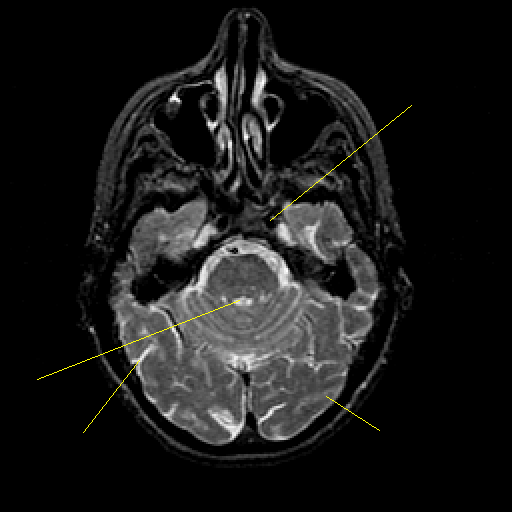

T2-weighted structural MR: Slice 16

Slice 16

Pointers

Labeled